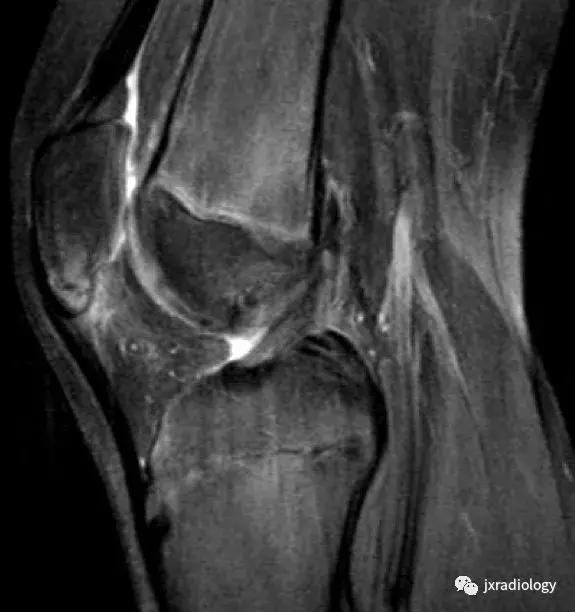

图4:SIF(软骨下不全性骨折):在过去,每当在股骨内侧髁上观察到这种软骨下病变时,它就被标记为膝关节自发性骨坏死(SONK)。现在它被认为是一个不全性骨折。这些不全性骨折通常发生在股骨内侧髁和股骨头,并存在于老年人中(它们与骨质疏松症和生物力学改变相关,如在不稳定的半月板损伤中。与其他应力性骨折类似,低信号的骨折线在水敏性序列(a,b:冠状和矢状PDWI-FS)上被高信号的骨髓水肿包围。